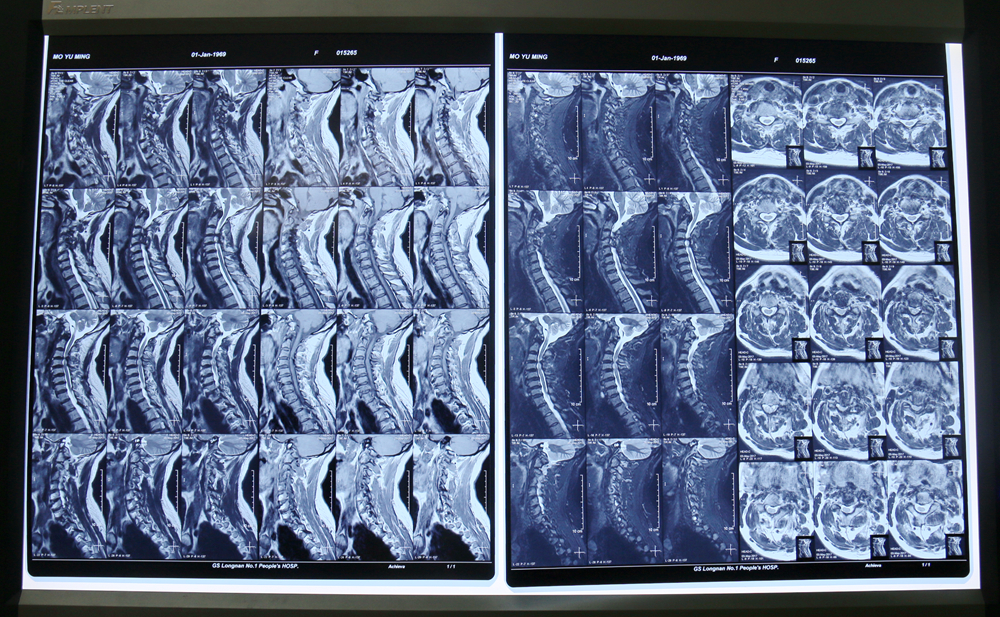

术前影像资料

患者,女,48岁,渐进性四肢肌力、感觉减退伴行走不便2月余。入院后行颈椎磁共振:颈3-4、4-5、6-7椎间盘突出,颈3-4、4-5椎间盘平面椎管狭窄,黄韧带肥厚。科主任协同主治大夫等人会诊后确定了手术方案,5月13日,在麻醉科的配合下,在全麻下行高位颈椎椎间盘突出并椎管狭窄后路减压侧块螺钉钉棒系统内固定术,术程顺利,患者术后恢复良好,现已佩戴护具下床。